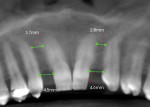

Limited maxillary fixed orthodontics were placed for a period of 8 months. A pre-orthodontic cone-beam computed tomography (CBCT) scan (CS 9300, Carestream Dental, carestreamdental.com) showed the roots of the central incisors and canines converged toward each other (Figure 3). A minimum distance of 6.2 mm would be needed for placement of a tapered 3.2 mm x 10.5 mm implant (Legacy2™ [3.2L2], Implant Direct, implantdirect.com). The pre-orthodontic scan (Figure 3) showed the space for No. 7 was 4.5 mm and the space for No. 10 was 4.6 mm.

A final CBCT was taken when sufficient space was established, and the positions of the teeth were stabilized for an additional 3 months. The post-orthodontic CBCT image (Figure 4) showed 6.2 mm of space at the No. 7 site and 6.8 mm of space at the No. 10 site to accommodate the impending implants.